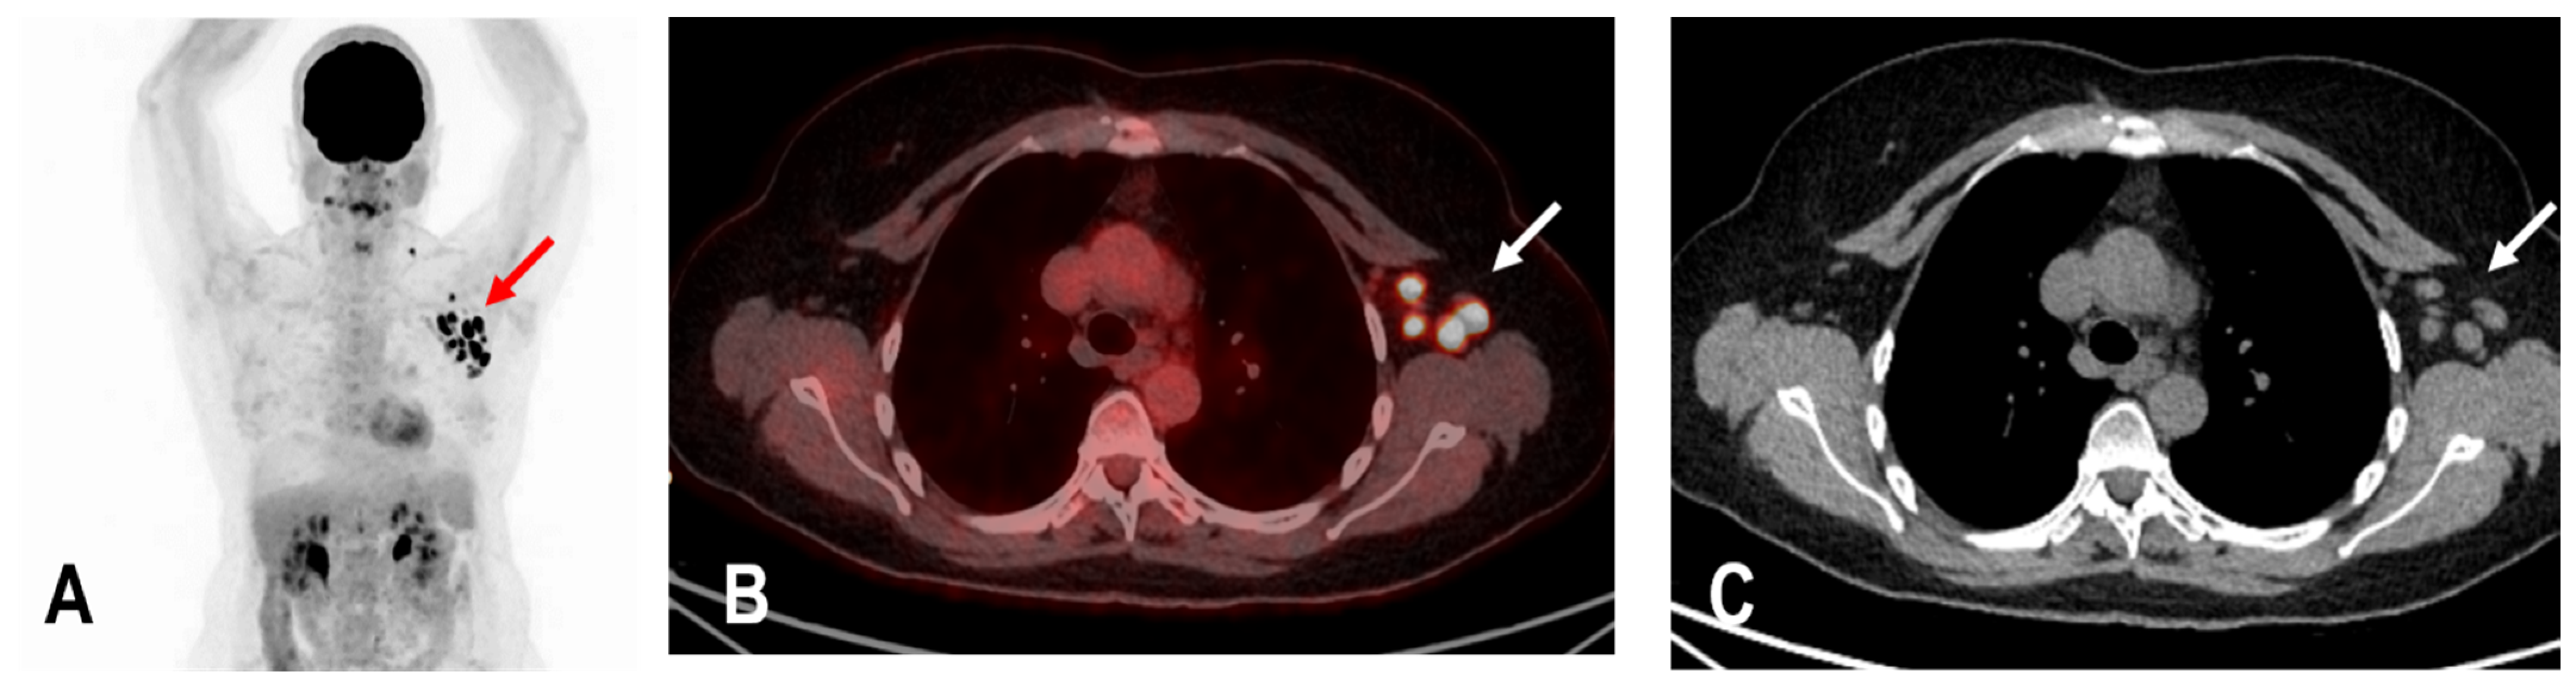

The widespread administration of such vaccines may pose diagnostic challenges in patients undergoing an 18F-FDG PET/CT as enlarged and hypermetabolic lymph nodes (HLA) following vaccination were frequently reported (Figure 4) [6,9,10].

Figure 4.

The maximum intensity projection (MIP) (A) of a patient with rectal carcinoma and HLA in the ipsilateral draining supraclavicular and axillary lymph nodes (red arrow) in the 18F-FDG PET/CT 10 days following COVID-19 vaccination. Fused images (B) show that the hypermetabolism is located in the moderately enlarged lymph nodes (white arrow) which still show a physiological fat hilus (SUVmax: 18.6, rHLA/MBP: 7.75, and rHLA/RL:11.6 (C)).